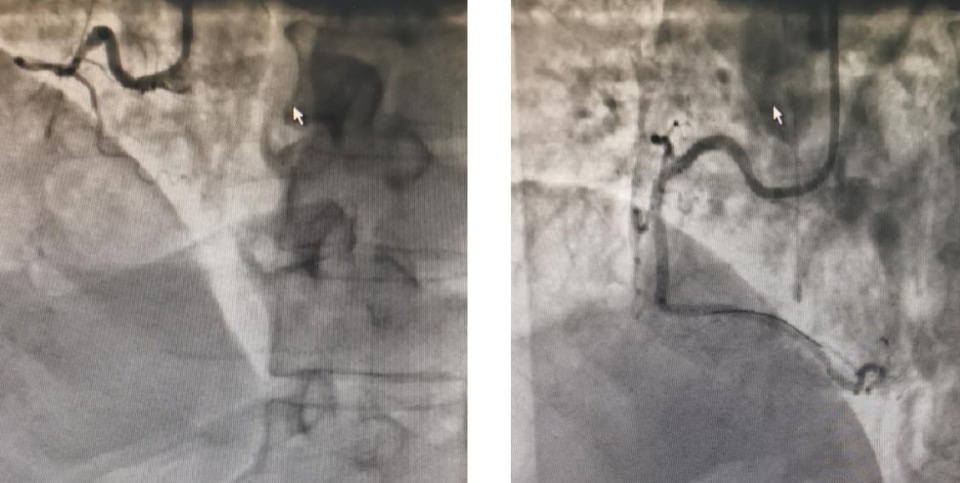

造影显示右冠状动脉近中段100%狭窄,前向血流TIMI0级。手术过程中植入两枚支架,转心内科CCU继续接受治疗。

△介入治疗前后对比照